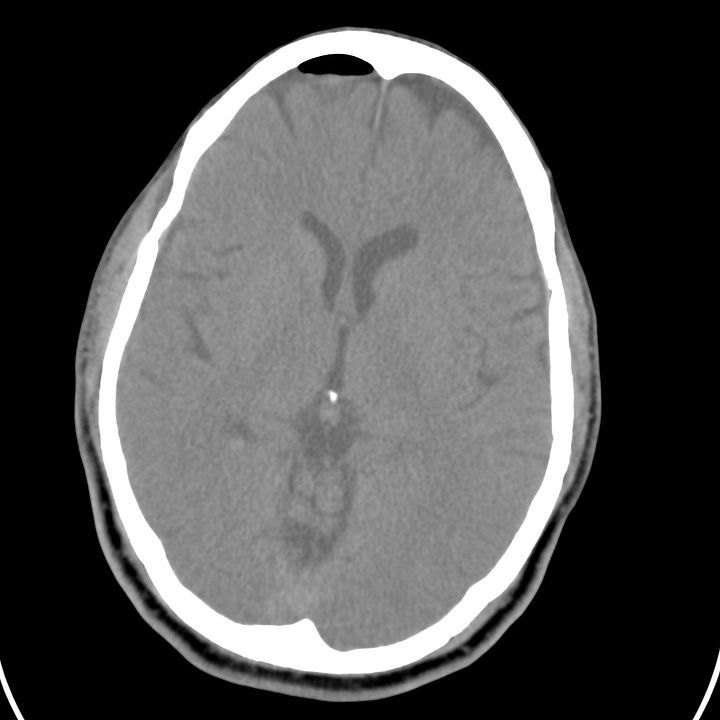

Pneumocephalus following facial trauma with orbital roof and ethmoid fractures. Small amount of air anterior to the right frontal lobe, between the ethmoid bone and the olfactory cortex, and within the right superior orbit. This air is not under tension, but it indicates that the skull base periosteum has been breached and that the subdural space communicates with one of the facial sinuses (in this case the ethmoid air cells). The patient is therefore at increased risk of CSF leak or meningitis.